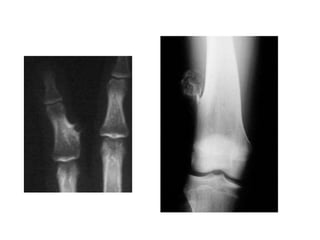

Quiste óseo simple

• Formación quística de localización

metafisiaria, unicameral.

• Edad de presentación :5-15 años

• Sexo: relación V/M: 2/1

• Localización: metafisiaria, extremidad superior

de humero, fémur y tibia.

• Clínica: dolor o fractura patológica.

• Radiología

– Formación osteolitica (radiolucida) circunscripta,

central, que afecta todo el diámetro del segmento

comprometido. Bordes netos, con esbozos de

trabeculatura o crestas en su interior.

• Histología

– Membrana fibrohistiocitiaria con algunas células

gigantes.

Ortopedia y traumatologia. Silverman , Varaona. Editorial Medica Panamericana. 2da edicion . Pag. 205-219